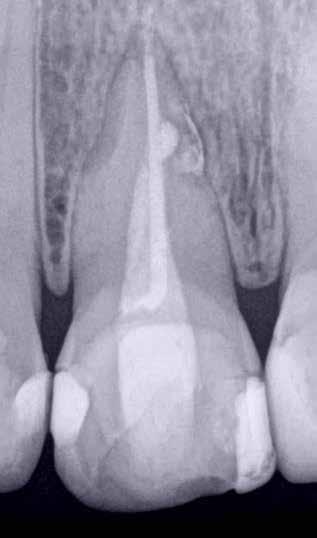

ai felvételek segítségével viszonylag jól el lehet különíteni a külső rezopció okozta ártalmaktól. A belső rezorpciótól szenvedő fogak esetében a radiológiai felvételek excentrikus irányból történő elkészítése során a rezorptív lézió a fog gyökércsatornájával egy irányba mozdul el a felvételen, míg külső rezorpció esetében le fog vetülni a gyökércsatornáról. 1999 márciusában egy 47 éves hölgy páciens arcduzzanattal kereste fel a rendelőnket. Klinikai vizsgálat során a jobb felső nagymetszőfog (11) kopogtatásra való érzékenységét tapasztaltuk. A felső front régióról készült periapikális felvételeken a frontfogakban lévő nagy kiterjedésű III. és IV. osztályú restaurátumokat észleltünk. Az 11-es fog gyökércsúcsa körül periapikális felritkulás volt látható. A 21-es fognál a gyökér középső harmadában belső rezorpciót észleltünk (13. ábra). A páciens kérdésünkre elmondta, hogy a bal felső nagymetszője közel 35 évvel ezelőtt traumás sérülést szenvedett. Mivel abban az időben CBCT-felvételek készítése nem volt számunkra elérhető, így a klinikai adatok alapján azt feltételeztük, hogy a rezorptív lézió bukkális irányba perforálta a gyökércsatorna falát, majd ezt követően az ezt a területet fedő bukkális csontállományt is destruálta.

A frontrégióban végzett szenzibilitás vizsgálat is megerősítette a 11 fogban a fogbélelhalás diagnózisát. Az 11-es fog endodonciai kezelése során a gyökércsatorna biokemo-mechanikai megmunkálását követően a gyökércsatornát meleg vertikális kondenzációs technikával zártuk. A bal felső nagymetsző esetében a gyökércsatorna megmunkálását a rezorpciós üreg koronális határáig végeztük, majd a megmunkált csatornaszakaszt fehér MTA-val töltöttük fel (14. ábra). Amennyiben ennek a fognak a kezelését ma kellene elvégezni, akkor az EndoSequence BC puttyt (Brasseler) használnánk a gyökértömés elkészítésére. Ezenkívül azt is megemlítenénk, hogy manapság egyre gyakrabban próbál-

13. ábra: A periapikális felvételen jól lekövethető a 11-es fog gyökércsúcsa körül látható radiolucens terület körvonala. A 21-es fog gyökerének középső harmadában pedig belső rezorpció jelenlétére utaló jelek észlelhetőek. A rezorptív lézió frontális és laterális irányban is áttörte a csontos falakat, amely következtében a gyökeret körülvevő csontállomány is károsodott. – 14. ábra: A posztoperatív felvételen jól megfigyelhető a 11-es fogba helyezett gyökértömés. A 21-es fog ellátása során a gyökércsatorna megmunkálását csak a rezorptív defektus koronális határáig végeztük. A gyökércsatorna zárására fehér MTA-t alkalmaztunk. – 15. ábra: A 11-es fog gyökércsúcsa körül látható felritkulás teljesen eltűnt. A rezorptív defektus mérete csökkent, valamint a rezorpciós üreg csontosodására utaló jelek is megfigyelhetőek. – 16. ábra: A saggitalis irányú CBCT-metszeten jól látható, hogy a 21-es fogat ép és jól megtartott bukkális kortikális csont fedi. A rezorpciós üreg mérete jelentősen csökkent, valamint az üreg kalcifikálódott anyaggal való telődése is megfigyelhető volt.

koznak a rezorptív léziók injektálható PRF-fel történő kezelésével. Az eddigi eredmények alapján ezzel az eljárással rendkívül kedvező hosszú távú eredményeket lehet elérni. A 21 évvel később készített kontrollfelvételeken látható, hogy az 11-es fog gyökércsúcsánál látható periapikális lézió teljesen eltűnt, valamint a rezorptív lézió mérete is jelentősen csökkent (15–16. ábra)